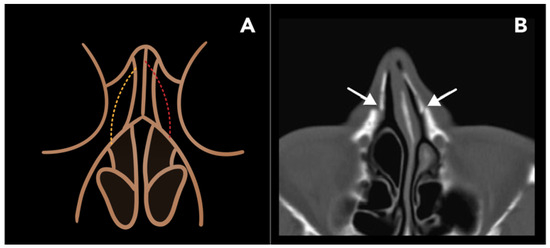

2.1.2. Lateral Nasal Osteotomy

- Ghanaatpisheh, M.; Sajjadian, A.; Daniel, R.K. Superior rhinoplasty outcomes with precise nasal osteotomy: An individualized approach for maintaining function and achieving aesthetic goals. Aesthetic Surg. J. 2015, 35, 28–39. [Google Scholar] [CrossRef]

- Hontanilla, B.; Cabello, A.; Olivas, J. A predictable approach for osteotomy in rhinoplasty: A new concept of open external osteotomy. Plast. Reconstr. Surg. Glob. Open 2016, 4, e764. [Google Scholar] [CrossRef] [PubMed]